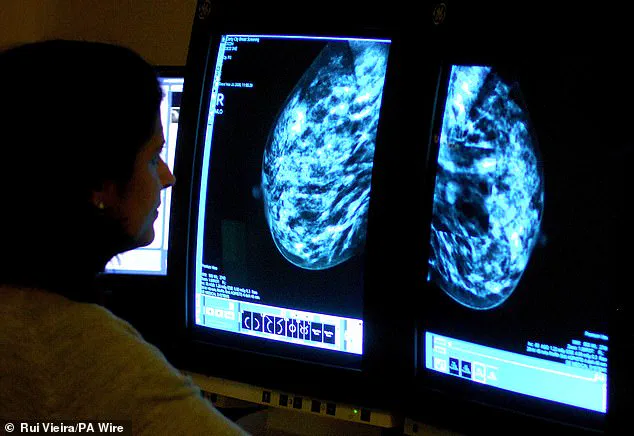

For some women, mammograms may be the only way their cancer is detected, especially if dense breast tissue is a factor.

Dense breast tissue, she explains, is a common but often overlooked risk factor.

It makes breast cancer harder to detect on mammograms, requiring additional imaging in many cases.

Research has increasingly highlighted the dangers of dense breast tissue, with over a million women in the UK at heightened risk as a result. 'Ask if your breast density is noted on your mammogram,' Dr.

Ramsey advises, emphasizing that this is a detail patients should not ignore.

The UK's national breast cancer screening programme, which invites women aged 50 to 70 for mammograms every three years, has long been a cornerstone of early detection efforts.

Yet a growing concern among medical experts is that the system is failing to address a critical factor in breast cancer risk: breast density.

Women identified as having dense breasts during routine mammograms are typically not informed of this finding, and in many cases, the information is not even recorded in their medical notes.

This omission has sparked debate, with advocates arguing that failing to communicate this detail could hinder early diagnosis and treatment planning.

Dense breast tissue, which refers to a higher proportion of fibrous and glandular tissue relative to fatty tissue, is a known risk factor for breast cancer.

Experts are increasingly calling for a fundamental shift in how breast density is handled within the screening programme.

Dr.

Ramsey, a leading oncologist, has highlighted the importance of informing women about their breast density and offering additional imaging tests, such as ultrasound or MRI, which may detect abnormalities that mammograms miss. 'The lifestyle changes people talk about really do make a difference,' she said, underscoring the interplay between biology and behaviour in cancer prevention.